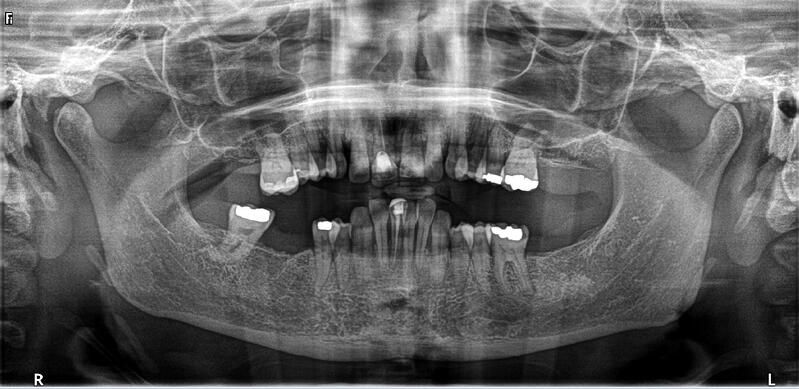

術(shù)前診斷